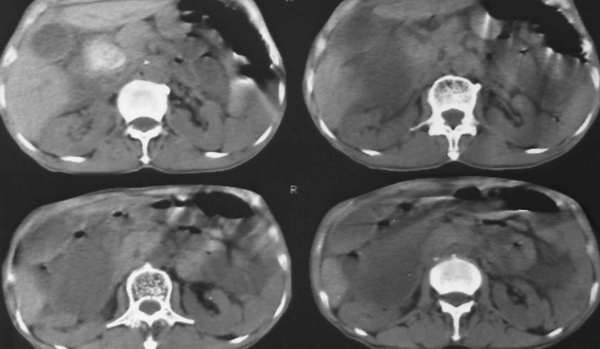

以下是引用lkc8963在2006-1-19 21:13:00的发言:[br]右半结肠及盆腔小肠明显积液扩张,腹腔内无明显渗出;右半结肠近端见多发点状高密度影;胆管内多发结石。[br]不知临床有哪些资料。本例需考虑胆石性肠梗阻的可能性,或胆系结石漏至结肠(异常通道如瘘)。

以下是引用wawaquan在2006-1-19 23:55:00的发言:[br]胆系结石,右半结肠梗阻:考虑横结肠占位(横结肠壁厚呈肿块状)。